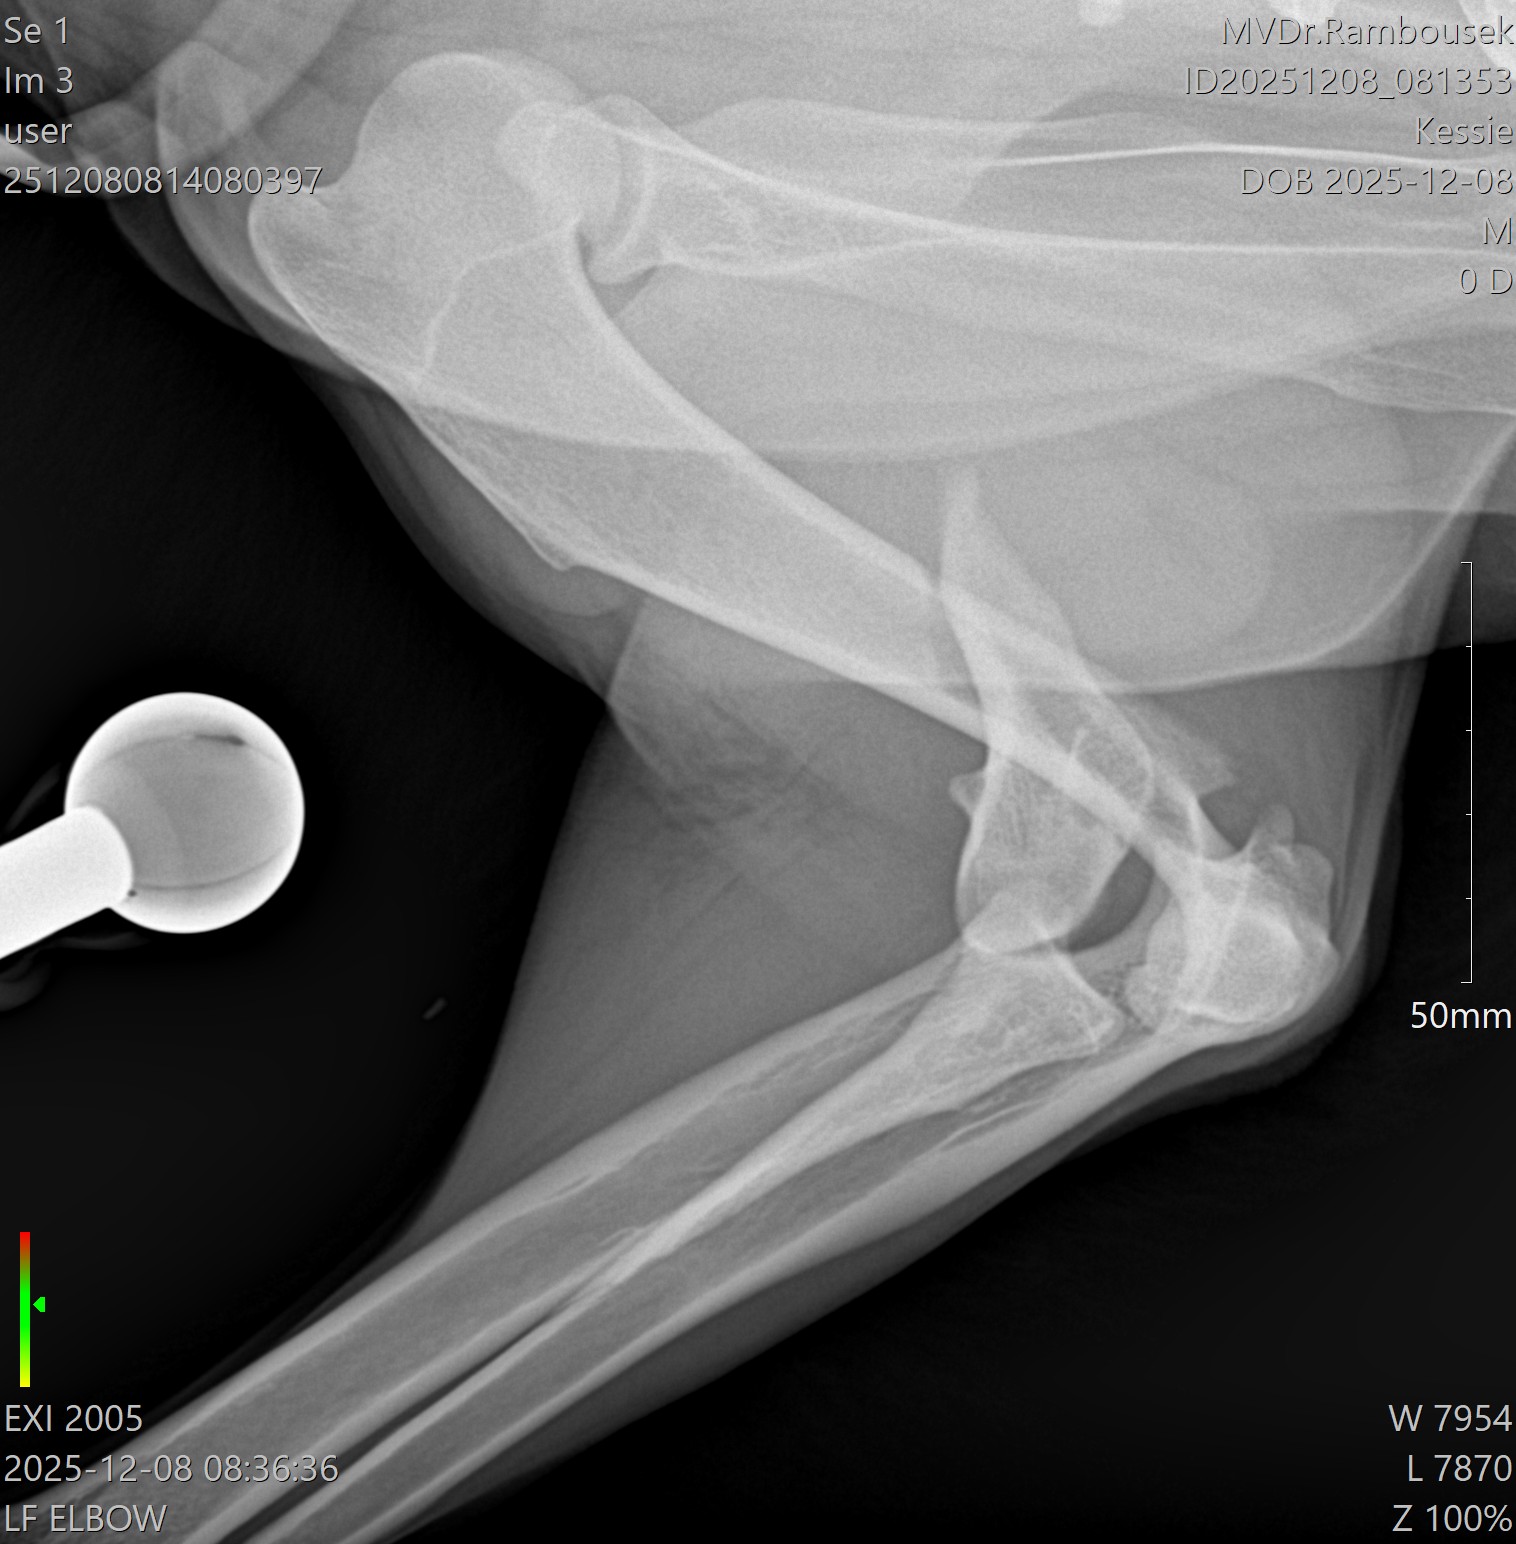

Fraktura pažní kosti - mediální kondylus

Případy z praxe

Akutní

případ